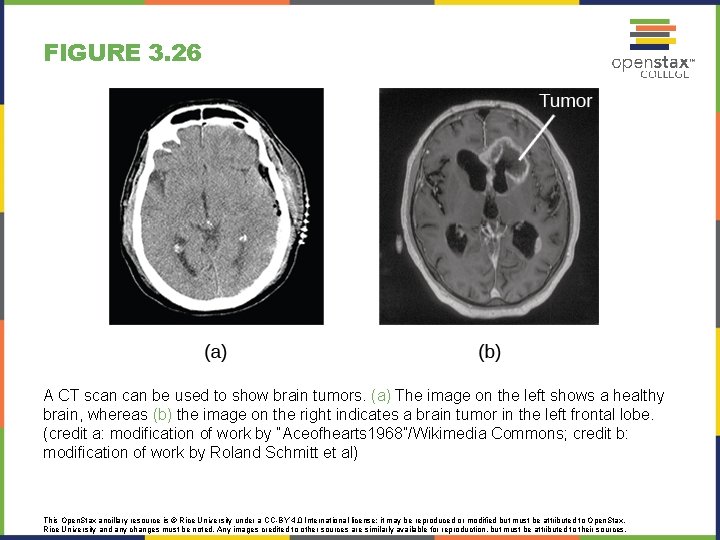

FIGURE 3. 26 A CT scan be used to show brain tumors. (a) The image on the left shows a healthy brain, whereas (b) the image on the right indicates a brain tumor in the left frontal lobe. (credit a: modification of work by “Aceofhearts 1968”/Wikimedia Commons; credit b: modification of work by Roland Schmitt et al) This Open. Stax ancillary resource is © Rice University under a CC-BY 4. 0 International license; it may be reproduced or modified but must be attributed to Open. Stax, Rice University and any changes must be noted. Any images credited to other sources are similarly available for reproduction, but must be attributed to their sources.